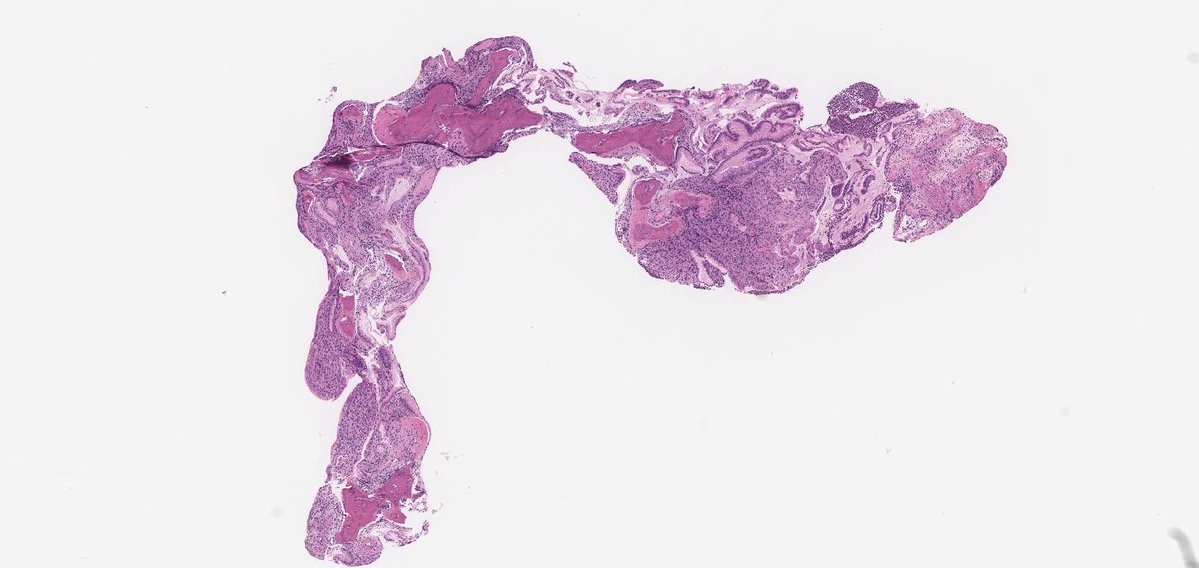

#GUpath #beautyinb9 mimic of prostate cancer on bx: 🔬basal cell hyperplasia